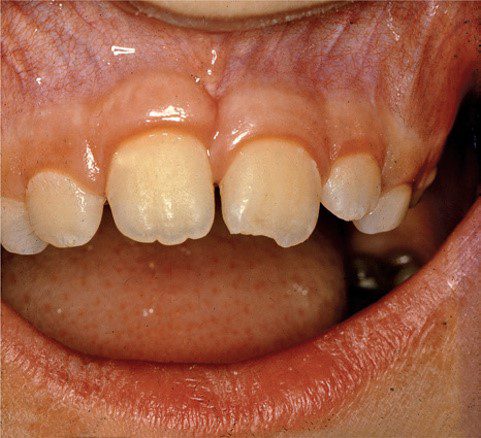

Gãy men và gãy men-ngà không liên quan đến tủy xảy ra thường xuyên ở cả răng sữa và răng vĩnh viễn. Chúng thường chỉ giới hạn ở một răng duy nhất, thường là các răng cửa giữa hàm trên. đặc biệt là các góc gần hoặc xa (Hình 13.3).

Đường gãy có thể nằm ngang theo chiều gần xa. Đôi khi chỉ liên quan đến thùy giữa của rìa cắn (Hình 13.4).